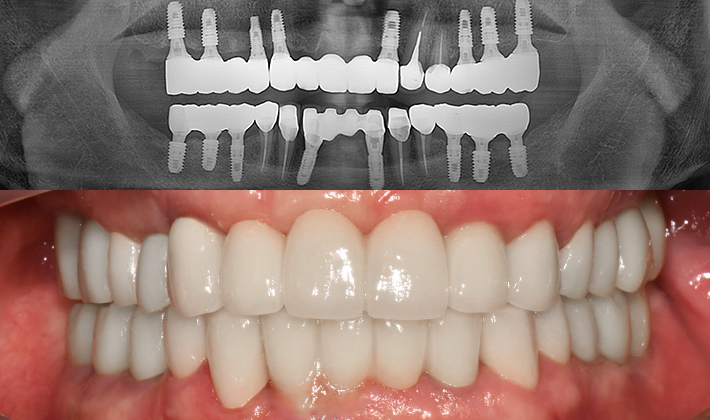

실제 치료 사례

수많은 환자들이 고민 끝에 선택한 치료,

그리고 그 후의 놀라운 변화

- ※ 위 임상사진은 365서울원탑치과에서 진료를 시작하고 마친 동일한 환자의 사진입니다.

- ※ 위 임상사진은 동일한 장소에서 동일한 조건으로 촬영되었으며, 사진에 대한 별도의 조작이 처리되지 않았습니다.

- ※ 수술 및 치료 과정에서 부작용이 발생할 수 있으므로 의료진과의 충분한 상담과 신중한 판단이 요구됩니다.